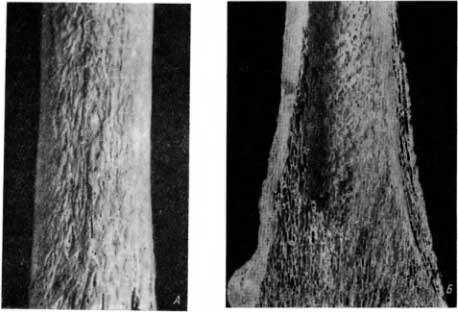

Поверхность диафиза бедренных и большеберцовых костей из-за своеобразно окостеневших периостальных наслоений была негладкой. Рисунок окостеневших периостальных наслоений отличался довольно правильной, но преимущественно продольной складчатостью (рис. 41, А). Эта складчатость напоминала кору старого дерева. Изменение рельефа особенно резко выражено в нижней трети большеберцовых костей, а также в нижней трети бедренных костей, почти на всем протяжении малоберцовых костей и на некоторых участках I пястной кости. Справа и слева в симметричных местах эти изменения были в общем одинаково выражены.

Рис. 41. А — проявления синдрома Мари — Бамбергера на поверхности бедренной кости, поверхность складчатая; Б — спонгиозная структура периостальных наслоений на большеберцовой кости при синдроме Мари — Бамбергера, ширина костномозгового пространства нормальная.

Как показывает фронтальный распил большеберцовой кости (рис. 41, Б), губчатое вещество не подверглось изменениям. Патология проявляется в окостеневших периостальных наслоениях, неравномерно охватывающих весь диафиз и частично дистальный метафиз. Во время распиливания кости часть окостеневших периостальных наслоений разрушилась. Сохранившиеся периостальные наслоения, хорошо видимые на фотографии, представлены спонгиозными пластинками с правильной мелкоячеистой структурой. Эти тонкие, нежные костные пластинки располагаются в основном параллельно друг другу и компактному веществу кости (рис. 41, Б). В среднем отделе диафиза костных наслоений значительно меньше.

Как видно на распиле, компактное вещество на всем протяжении не утолщено, а костномозговые пространства не сужены. Следовательно, периостальные наслоения не были ассимилированы компактным веществом. Ассимиляция периостальных наслоений, ведущая к утолщению компактного вещества, характерна для ряда патологических процессов, в частности сифилитического происхождения. При синдроме Мари— Бамбергера этого, однако, не бывает.

На распиле видно, что периостальные наслоения неравномерно выражены на поверхности кости: их больше на внутренней, чем на наружной поверхности (рис. 41, Б).